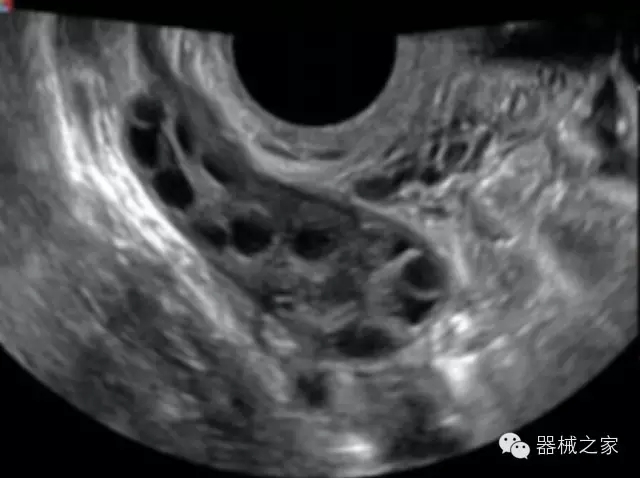

臨床圖片賞析

產(chǎn)品特點

優(yōu)異的成像技術(shù)

·亞陣元技術(shù):獨有的亞陣元技術(shù),對獨立晶片做二次切割,減少旁瓣偽像,增加臨床診斷的準(zhǔn)確性;

·μ-Scan微米成像技術(shù):開立獨有的μ-Scan技術(shù),還原出真實細(xì)膩、層次對比優(yōu)異的二維圖像;

·倒相諧波成像技術(shù):倒相諧波技術(shù)在去除基波信號的基礎(chǔ)上獲取兩倍二次諧波信號,提高組織圖像的對比分辨力;

·智能微血流成像技術(shù):智能微血流捕捉技術(shù)可以提取出隱藏在背景噪聲中的弱血流信號,大大提高低速血流的敏感性;

·高效3D/4D成像技術(shù):高速的4D幀頻,豐富的3D成像模式,智能斷層切片功能;

·獨有的大角度及實時溫控技術(shù),能同一切面顯示宮頸及宮體,有效減低了患者的痛苦,及保護(hù)粘膜保證了醫(yī)療安全;